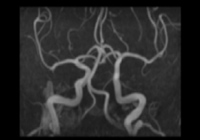

| 脳の血管を撮影し主幹動脈を見ます。無症候性脳梗塞、血管の狭窄などを撮影いたします。 | ||